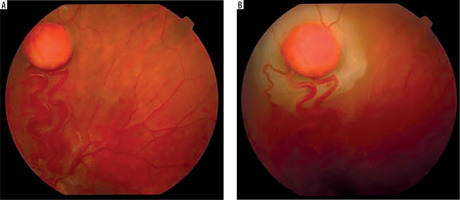

It is a very rare disease, affecting an estimated one in 30,000–40,000 individuals, with around 1,000 cases reported in Poland. The condition is inherited in an autosomal dominant manner. The syndrome is caused by constitutional mutations of the VHL tumor suppressor gene located on the short arm of chromosome 3. Constitutional mutations affecting a single gene are present in all cells of the body and represent the primary cause of pathology in this type of genetic disorder. The syndrome is characterized by the presence of hemangioblastoma-type tumors in the cerebellum, spinal cord, brain, visceral organs, and the eye [16]. The tumors consist of components of hemangioblastomas [6]. Visceral abnormalities are associated with the presence of pancreatic and renal cysts, as well as polycythemia. Tumors such as pheochromocytoma and adenocarcinoma may also occur. Hemangioblastomas that develop in the brain and spinal cord can cause headaches, vomiting, weakness, and loss of muscle coordination (ataxia). Within the ocular globe, capillary malformations affecting the optic nerve and retina are detected. The malformations appear as tumors in both eyes, located peripherally and centrally [6] (Figure 8A, B). Peripheral distribution is characterized by the presence of tortuous, dilated vessels that supply and drain blood from the tumor. In contrast, centrally located vascular tumors typically exhibit an endophytic growth pattern and lack afferent and efferent vessels associated with vascular malformations. Disease progression may lead to retinitis and retinal detachment, iridocyclitis, and rubeosis iridis. The changes may result in the development of secondary glaucoma.

Figure 8A, B

Retinal vascular malformation in von Hippel-Lindau syndrome – before treatment and during therapy